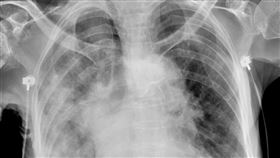

氧氣用到100%!台商「大白肺」死亡率4成

蘇一峰醫師在個人臉書發文並貼出一張「大白肺」X光片,...

2023/01/07 12:02

本土確診白肺插管 胸腔醫嘆:沒床位可去

北市聯合醫院胸腔內科主治醫師蘇一峰近日在臉書上貼出一...

2023/01/11 06:54